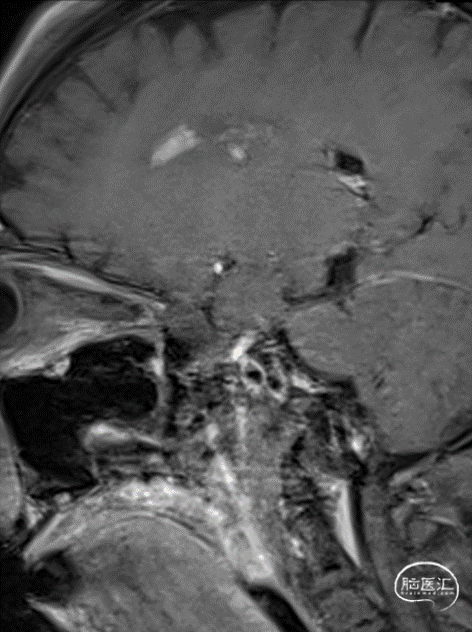

MR提示:右侧半卵圆区新发脑梗死(A、B)。

头颅CTP:右侧大脑中动脉区域明显低灌。

术前行高分辨率核磁共振:右侧大脑中动脉前壁强化斑块。

2. 头MRI示右侧半卵圆区新发脑梗死,右侧大脑中动脉M1段闭塞;代偿不佳,CTP示右侧大脑半球低灌注;高分辨率核磁共振:右侧大脑中动脉前壁强化斑块。